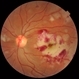

- Condition/keywords

- retinal ischemia

- This patient with long standing diabetes has peripheral non-perfusion.